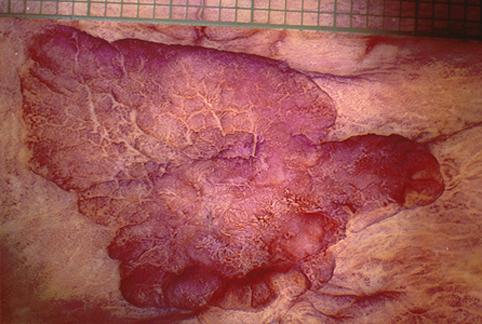

部位(按器官分)大肠/盲肠

检查方法切除标本(宏观)

肿瘤的肉眼分类0型(表在型)/其他

肿瘤最大直径20~24

肿瘤的深度sm